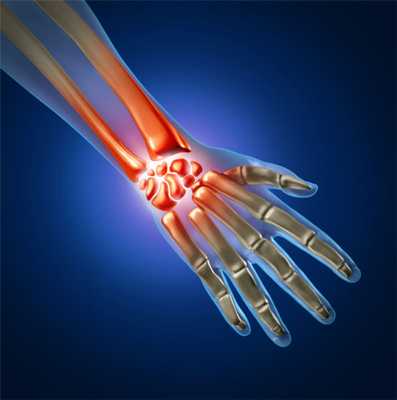

Вывих - противоестественное состояние, при котором происходит полное смещение суставных поверхностей относительно друг друга. Вывихи костей в кистевом суставе - это менее 5% от общего числа вывихов. Данные травмы случаются в лучезапястном суставе. Лучезапястный сустав представляет собой: с верхней стороны - лучевую и локтевую кости, а с нижней стороны - восемь маленьких косточек кисти. Восемь этих косточек, располагаясь в два ряда, и создают запястье. В большей мере травмы запястья происходят с полулунной и ладьевидной костями, реже встречаются вывихи других костей кисти.

Лучезапястный сустав - сложное подвижное соединение костей кисти и предплечья, которое обеспечивапе6т многообразие действий. Данный участок отличается уязвимостью, так как принимает на себя силовые нагрузки различной интенсивности. Один из наиболее часто встречающихся видов повреждений лучезапястного сустава - вывих. При вывихе смещаютсяи полностью теряют контакты суставные концы.

Лучезапястный сустав - это костное сочленение, которое образуют лучевая кость и три кости запястья: полулунная, ладьевидная и трехгранная. Данный сустав соединяет кисть и предплечье. С наружной стороны сустав укрыт прочной оболочкой (суставной сумкой). Суставная сумка с помощью связок прикрепляется с одной стороны к костям кисти, а с другой - к лучевой кости и суставному диску. Лучезапястный сустав - особо подвижное соединение костей верхней конечности: предплечья и кисти человека. Этот сустав является сложным по составу входящих в него костей, отвечает за многообразие действий в руке (вращательную функцию кисти руки, за сгибание, разгибание, отведение и приведение кисти) и принимает на себя различные силовые нагрузки, поэтому данный участок очень уязвим.